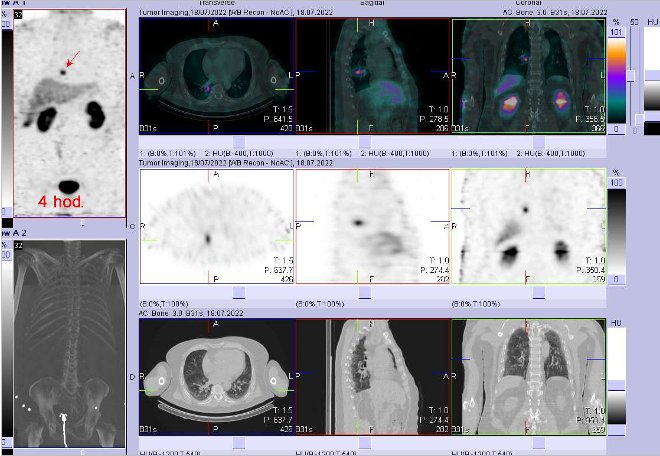

/ Obr. č. 2: Fúze SPECT/CT 4 hod. po aplikaci OctreoScanu. Zaměřeno na ložisko v pravé plíci.

Pozorujeme solitární patologické ložisko zvýšené depozice radiofarmaka na pomezí středního a dolního plicního pole dorzálně a mediálně (paravertebrálně – zřejmě v segmentu VI, koreluje s denzním přibližně kulovitým ložiskem na CT velikosti v průměru cca 10 mm). Nález svědčí pro tkáň se zvýšenou denzitou somatostatinových receptorů – solitární plicní metastázu.

U 61letého pacienta s neuroendokrinním tumorem kaudy pankreatu prokazujeme solitární metastázu v pravé plíci.